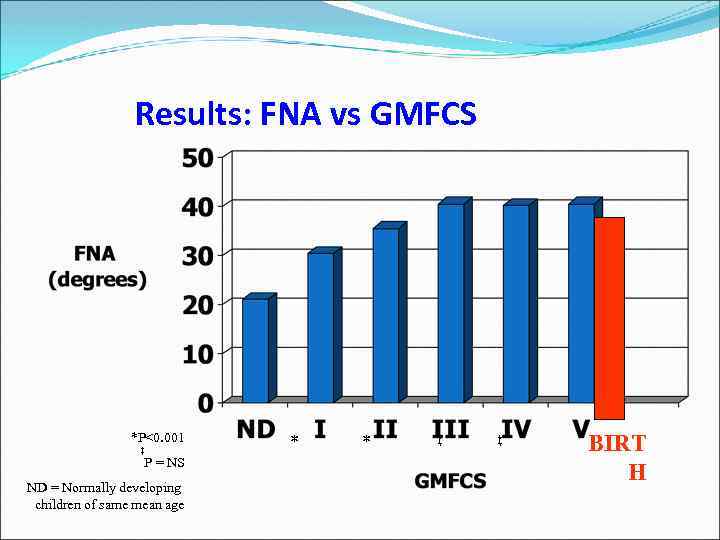

Results: NSA vs GMFCS * *P<0. 001 ND = Normally developing children of same mean age * * *

Results: FNA vs GMFCS *P<0. 001 ‡ P = NS ND = Normally developing children of same mean age * * ‡ ‡ BIRT H